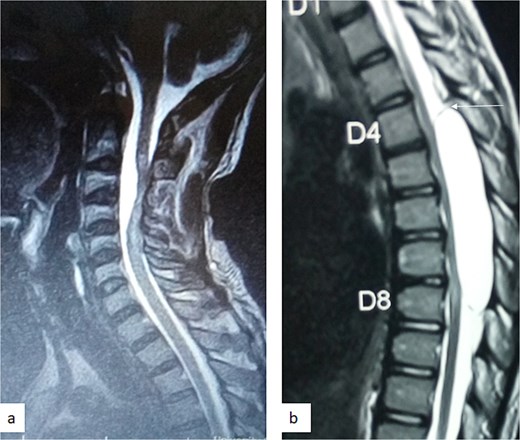

A 12-year-old girl presented to us with progressive weakness of the lower limbs of 11 months duration. There was associated paraesthesia and spasms but no sphincteric dysfunction. Clinical examination revealed an otherwise healthy young girl with normal mental status. She had spastic paraparesis (power Grades 3 to 4) and exaggerated muscle stretch reflexes in the lower limbs. The sensory level was T4. There was no gibbus or spinal tenderness. Other systemic examination findings were normal. A clinical diagnosis of T4 non-traumatic myelopathy, Frankel D was made. Thoracic spine MRI showed an extradural lesion with similar intensities to CSF on all sequences posterior to the spinal cord at T4–T8 as well as significant cord compression at the same levels (Fig. 3) [12]. A diagnosis of thoracic spine EAC was made. We approached the lesion through T4–T8 laminectomies. Intra-operative finding was that of a large extradural cyst which communicated with the subarachnoid space through a dorsolaterally located pedicle near the nerve sleeve at T7. The cyst was excised completely and the dura defect closed without duroplasty (Fig. 4) [12]. The post-operative course was uneventful and she was discharged on the 24th post-operative day. She was last seen 48 months post-surgery. At the time, she was ambulating without support with power of Grade 5 in the lower limbs.

Sagittal T1-weighted (a) and T2-weighted (b) thoracic spine MRI showing an extradural cyst at T4–T8 compressing the cord anteriorly [12].

MRI is the imaging modality of choice for the diagnosis and follow-up of SACs [4]. It does not require intrathecal injection of contrast and demonstrates the location, size, extent, and nature of the cysts as well as neural elements compression and intrinsic cord changes among other features [7, 16–18]. On MRI SACs have similar signal intensities to those of CSF, hypointense on T1-weighted, and hyperintense on T2-weighted images [16]. Extradural cysts may show absent posterior epidural fat, epidural fat capping, and T2-hypointense cyst wall [16, 19, 20] (Figs 3 and 6b). Intradural cysts are characterized by widening of the subarachnoid space, displacement of the cord/cord compression and an undistinguishable cyst wall [2, 21] (Fig. 1). The site of communication between the cysts and subarachnoid may not be demonstrable on MRI [16]. Computed tomography myelograghy has been the imaging of choice in demonstrating the communicating site between the cyst and the subarachnoid cyst [16]. Newer MRI flow studies using cinematic MRI has proven to also be able to demonstrate the communication site [22].

(a) Sagittal T2-weighted cervical spine MRI image showing expanded subarachnoid space anterior to the spinal cord at C2–C4, posterior displacement and compression of the cord and cord signal change at C2–C5. The wall of the cyst is indistinguishable suggestive of intradural spinal arachnoid cyst. (b) Sagittal T2-weighted thoracic MRI image showing compression of the spinal cord anteriorly. There is visible hypointense cyst wall (arrow) suggestive of extradural cyst.